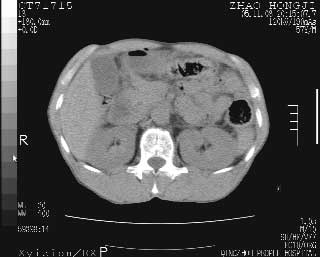

临床资料:男性,57岁,上腹部疼痛并5天,突然加重并延及全腹伴恶心5小时入院。胰淀粉酶化验在正常范围。检查:腹肌紧张,全腹压痛、反跳痛,尤以右上腹部为著。肠鸣音减低。血常规:wbc14.6x10/9, n:11.3x10/9 ,血压:135/90mmhg. 胸部透视:腹部肠腔轻度张气,未见其它异常改变。

肝右前缘少量积气,其他未见明显异常.考虑上消化道穿孔.

小网膜囊积气液,胃壁僵硬。考虑胃穿孔。

小膜网膜积液,肝缘气腹征,上消化道穿孔。

胰腺形态规则,胰周脂肪间隙清晰,结合临床可排除急性胰腺炎

肝脏前缘见少量积气、胰尾部见少许气体包饶,肾前筋膜未见增厚,临床淀粉酶不高,意见:上消化道穿孔。